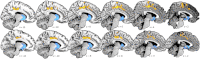

Individual differences in cognitive style can be characterized along two dimensions: 'systemizing' (S, the drive to analyze or build 'rule-based' systems) and 'empathizing' (E, the drive to identify another's mental state and respond to this with an appropriate emotion). Discrepancies between these two dimensions in one direction (S>E) or the other (E>S) are associated with sex differences in cognition: on average more males show an S>E cognitive style, while on average more females show an E>S profile. The neurobiological basis of these different profiles remains unknown. Since individuals may be typical or atypical for their sex, it is important to move away from the study of sex differences and towards the study of differences in cognitive style. Using structural magnetic resonance imaging we examined how neuroanatomy varies as a function of the discrepancy between E and S in 88 adult males from the general population. Selecting just males allows us to study discrepant E-S profiles in a pure way, unconfounded by other factors related to sex and gender. An increasing S>E profile was associated with increased gray matter volume in cingulate and dorsal medial prefrontal areas which have been implicated in processes related to cognitive control, monitoring, error detection, and probabilistic inference. An increasing E>S profile was associated with larger hypothalamic and ventral basal ganglia regions which have been implicated in neuroendocrine control, motivation and reward. These results suggest an underlying neuroanatomical basis linked to the discrepancy between these two important dimensions of individual differences in cognitive style.